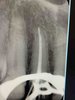

• Работа с дентальным рентгеном, радиовизиографом

Анализ прицельных рентген-снимков, ОПТГ, КТ.

Проведение и анализ снимков на визиографе и рентген-аппарате.